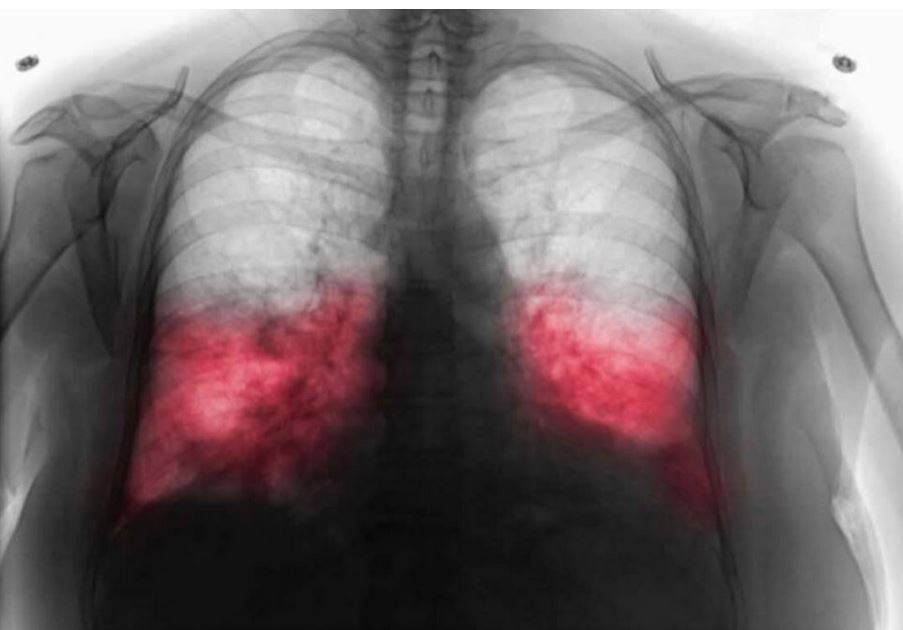

U današnjem članku vam donosimo tekst o temi koja je posljednjih sedmica privukla veliku pažnju javnosti, a to je povećan broj slučajeva takozvane hodajuće upale pluća. Iako naziv zvuči neobično, riječ je o obliku atipične upale pluća koji se može dugo razvijati bez dramatičnih simptoma, zbog čega mnogi ljudi nastavljaju sa svakodnevnim aktivnostima misleći da imaju samo prehladu ili blažu virozu.

Hodajuću upalu pluća najčešće izaziva bakterija koja napada respiratorni sistem i postepeno stvara upalu u plućima. Ono što je karakteristično jeste da početak bolesti može biti veoma blag. Osoba može osjećati umor, blago grebanje u grlu ili temperaturu koja dolazi i prolazi. Mnogi se tada odluče da ostanu kod kuće, popiju čaj, uzmu nešto protiv bolova i nastave sa uobičajenim obavezama, a da pritom ne shvate da se infekcija razvija sve dublje. Zbog toga ljekari naglašavaju važnost prepoznavanja ranih znakova i pravovremenog javljanja doktoru.

Ljekari ističu da se hodajuća upala pluća ne smije ignorirati. Iako se simptomi čine blažim nego kod obične upale pluća, komplikacije mogu biti ozbiljne, posebno ako se liječenje odgodi. Najvažnije je obratiti se ljekaru čim primijetite da simptomi traju duže od nekoliko dana, posebno ako se kašalj pojačava, disanje postaje otežano ili se osjećate neobično umorno. Doktor može jednostavno pregledom i po potrebi dodatnim testovima utvrditi da li se radi o upali pluća i odrediti terapiju.